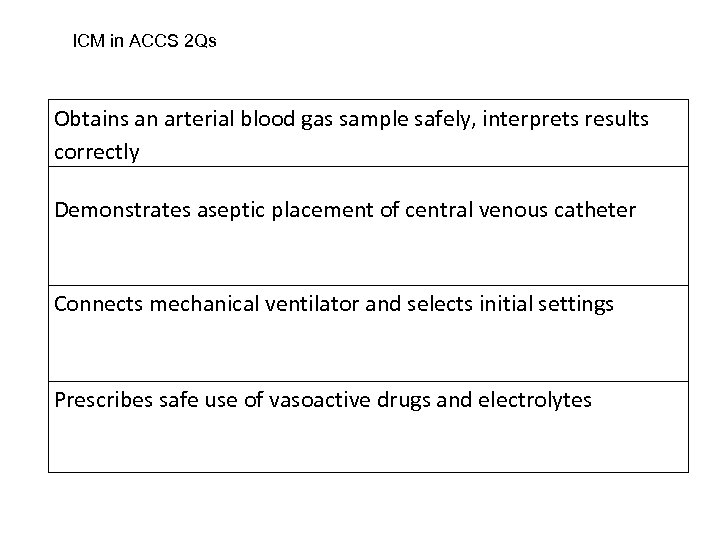

ICM in ACCS 2 Qs Obtains an arterial blood gas sample safely, interprets results correctly Demonstrates aseptic placement of central venous catheter Connects mechanical ventilator and selects initial settings Prescribes safe use of vasoactive drugs and electrolytes